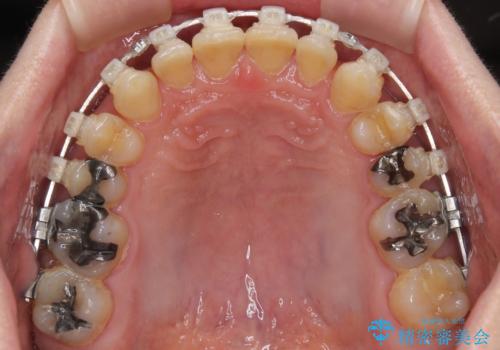

【モニター】ディープバイトで隙間の空いた歯列 ワイヤー装置での非抜歯矯正

- 前歯のデコボコと隙間の空いた歯列を気にして来院された患者様です。

下顎前歯が隠れるほどのディープバイトにより、強い咬合力と突き上げで上顎歯列に隙間が空いている状態でした。

手前に傾斜している奥歯をワイヤー装置で立ち上がらせ、咬み合わせの高さを挙上することで突き上げを解消し、空隙歯列を改善していくこととしました。